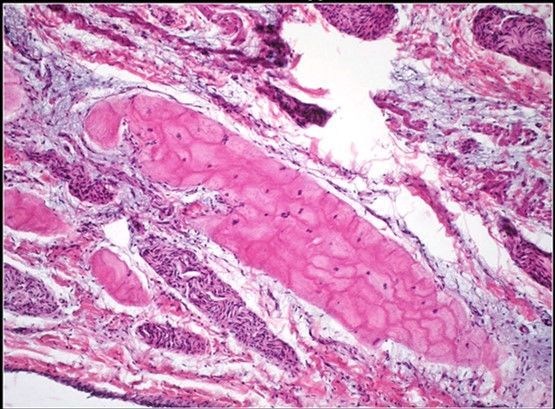

Question 4

Question

Label this Image First Dot: Name Second Dot: Staining

Image:

04ac7b1e-262e-4dcc-b6b3-8695c03316eb (image/jpeg)

Answer

Cardiac Striated Muscle Tissue

HE